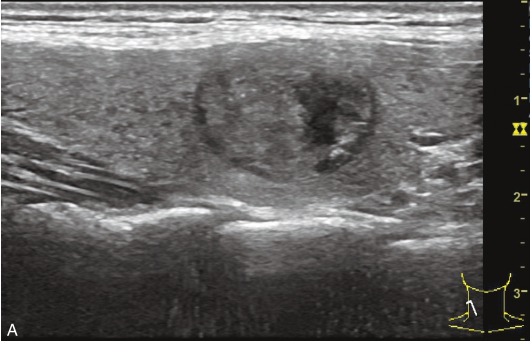

男性,64岁,体检发现甲状腺结节1天。体格检查:甲状腺无明显肿大。

甲状腺左叶中部实性中等回声,边缘光整,纵横比<1,内未见明显强回声,CDFI:结节内见血流信号,见图1-3-9。

图1-3-9 结节性甲状腺肿常规超声声像图

A.甲状腺左叶纵切面;B.CDFI血流图

甲状腺左叶中部结节15s开始增强。增强早期与周围正常甲状腺组织呈同步等增强,内部增强不均匀,增强后结节边界清,形态规则,周边可见环状高增强,增强晚期呈不均匀性低增强,见图1-3-10、ER1-3-5。

结节性甲状腺肿超声造影表现为病变多与周围正常甲状腺组织呈同步等或高增强,增强多较均匀,伴有囊性变者,内部可见无增强区,增强后结节边界清,周边可见环状增强,增强晚期呈等或稍高增强,也可呈稍低增强。

图1-3-10 结节性甲状腺肿超声造影图

A.增强早期结节呈同步不均匀性等增强;B.增强晚期呈不均匀性低增强